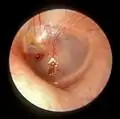

Right eardrum as seen through a speculum

Rupture

Unintentional perforation (rupture) has been described in blast injuries[9] and air travel, typically in patients experiencing upper respiratory congestion or general Eustachian tube dysfunction that prevents equalization of pressure in the middle ear.[10] It is also known to occur in swimming, diving (including scuba diving),[11] and martial arts.[12]

Patients with tympanic membrane rupture may experience bleeding, tinnitus, hearing loss, or disequilibrium (vertigo). However, they rarely require medical intervention, as between 80 and 95 percent of ruptures recover completely within two to four weeks.[13][14][15] The prognosis becomes more guarded as the force of injury increases.[15]